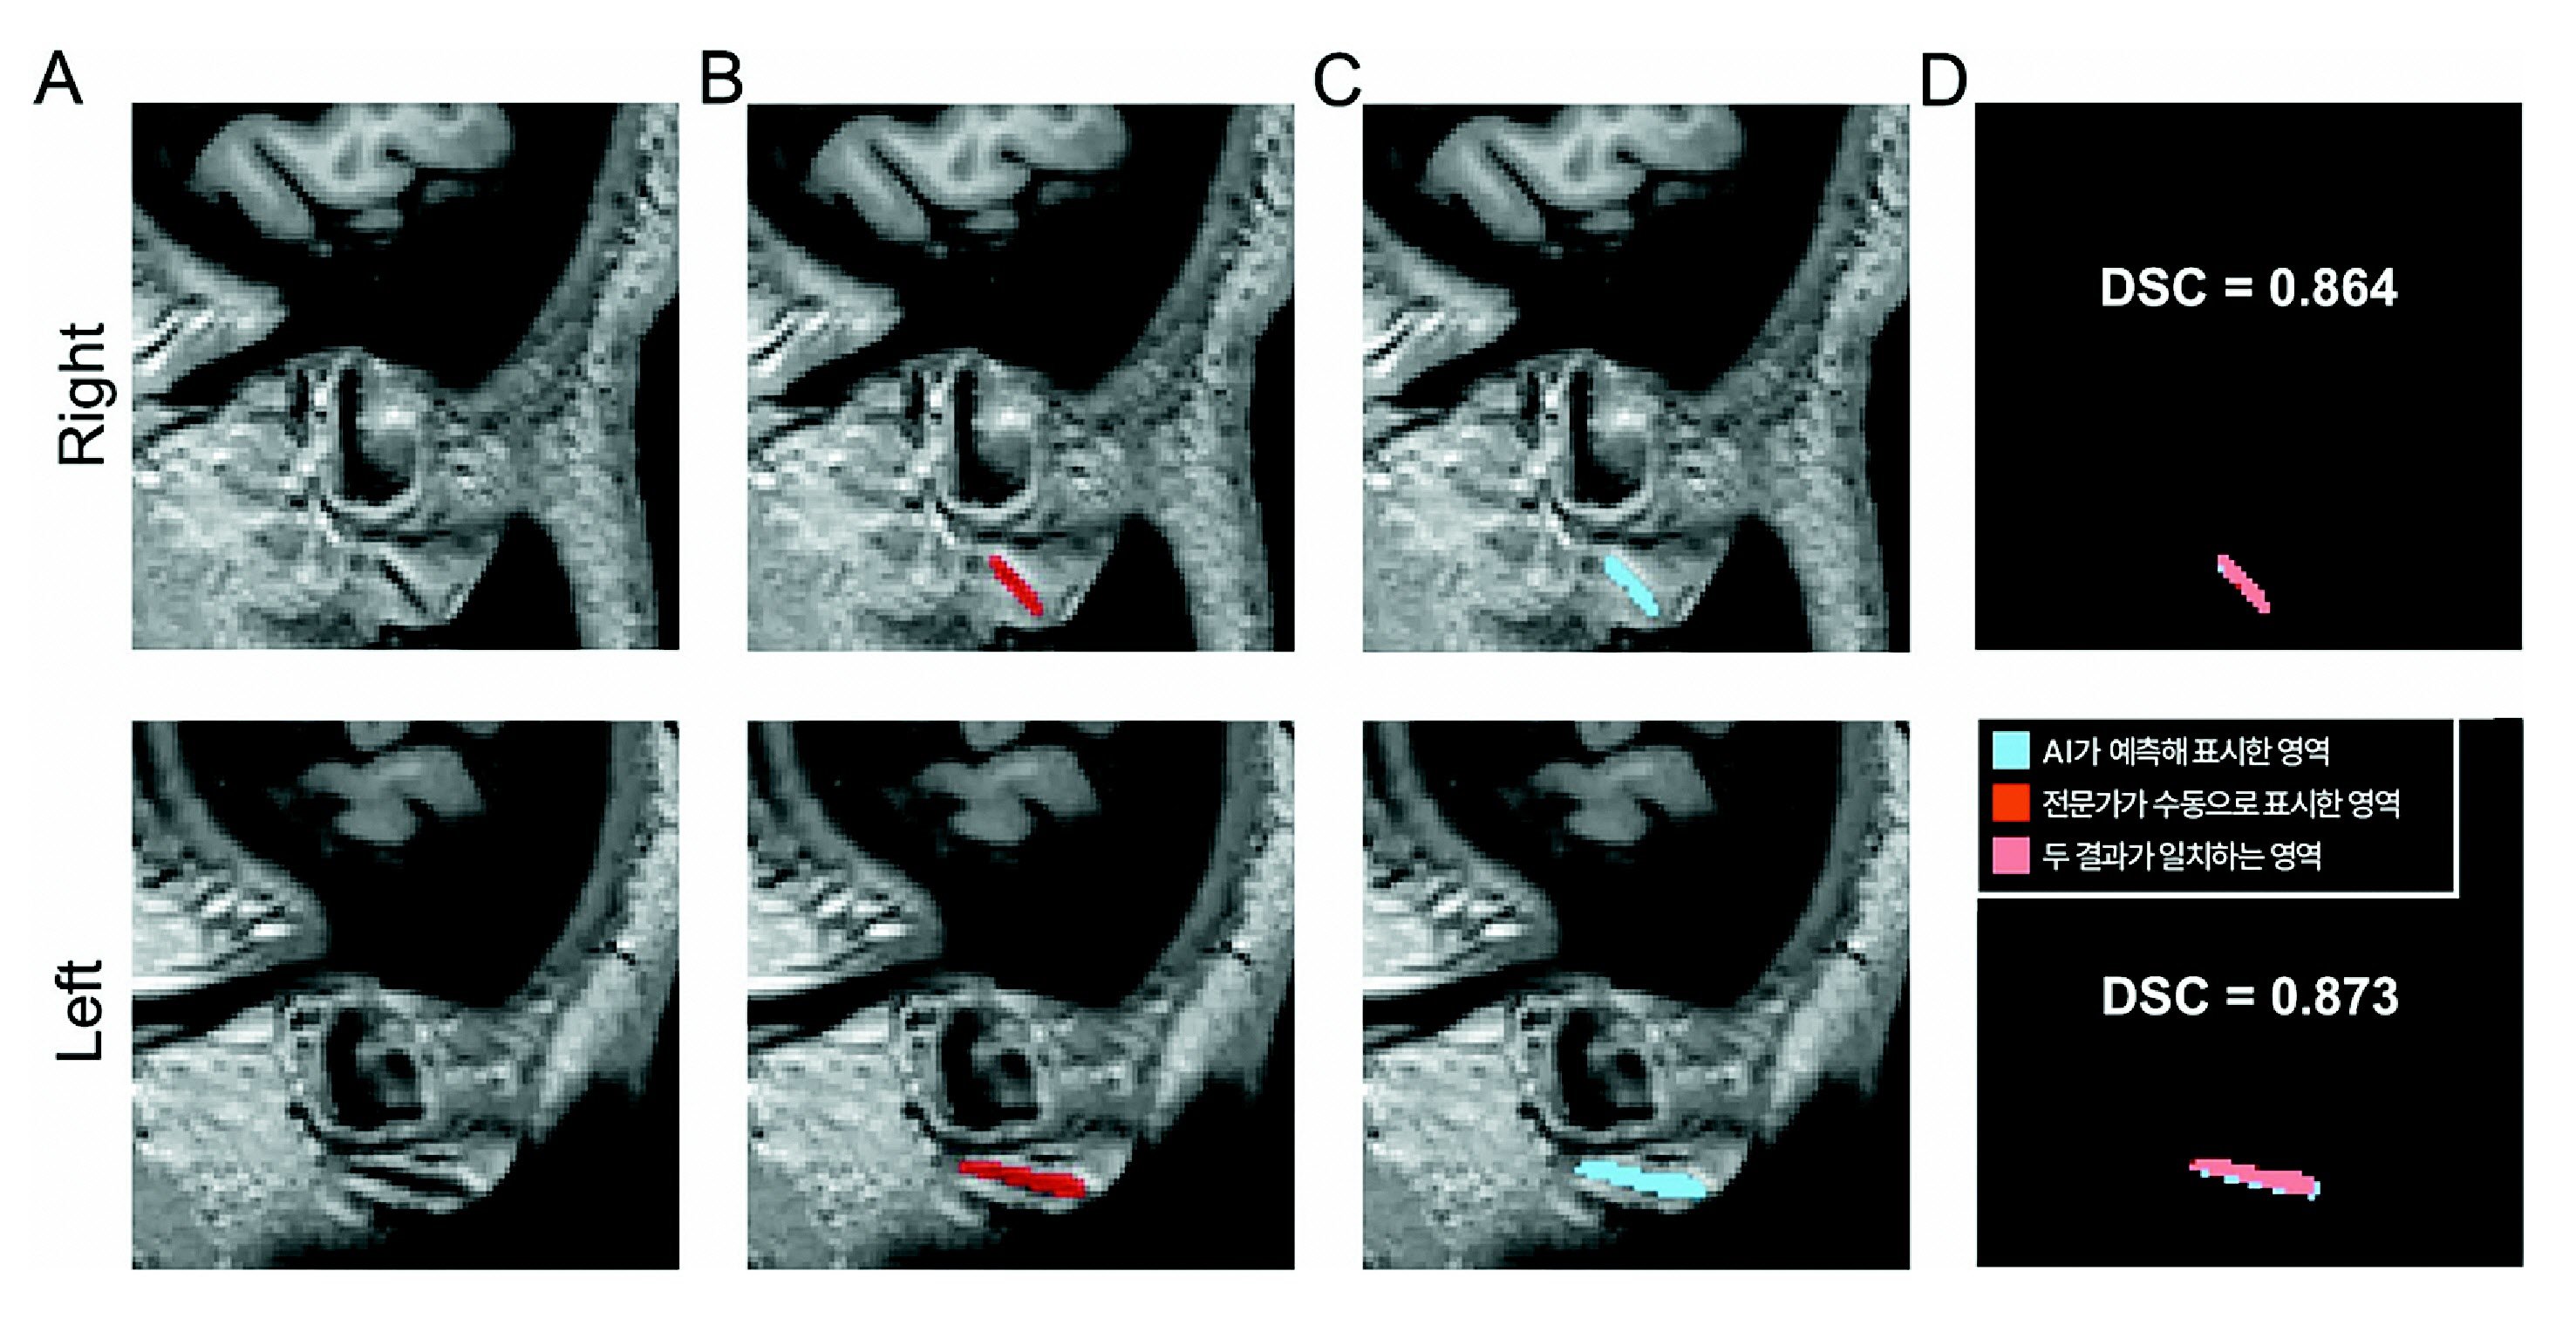

3차원 원본 이미지(A)를 토대로 전문가가 수동으로 직접 표시한 주름(B)과 AI가 예측해 자동으로 표시한 영역(C).

이 같은 한계를 보완하기 위해 분당서울대병원 정신건강의학과 김기웅 교수팀은 세계 최초로 3차원 뇌 자기공명영상(MRI)에서 프랭크 징후를 자동으로 탐지하는 AI 모델을 개발했다. 연구팀은 뇌 MRI 촬영 시 양쪽 귓불을 포함한 얼굴이 함께 촬영된다는 점에 착안해 MRI에서 추출한 3차원 얼굴 이미지를 활용했다.

분당서울대병원에서 수집한 뇌 MRI 400건을 바탕으로 전문가가 프랭크 징후를 수동으로 표시한 데이터를 AI에 학습시켰다. 이후 학습에 사용하지 않은 분당서울대병원 데이터 600건으로 1차 검증을 진행했고, 충남대병원·강원대병원·세브란스병원 등 다기관 데이터 460건으로 2차 검증을 실시했다.

검증에서는 전문가가 표시한 주름 영역과 AI가 자동으로 분할한 영역의 일치 정도를 비교했다. 그 결과 두 영역의 유사도를 나타내는 DSC(Dice 유사도 계수) 값은 각각 0.734와 0.714로 나타났다. 의료 영상 분야에서 0.7 이상은 높은 정확도로 평가된다. 프랭크 징후의 유무를 구분하는 성능을 나타내는 AUC(곡선 아래 면적) 값 역시 모두 0.9 이상을 기록해 다양한 임상 환경에서도 안정적으로 작동할 수 있음을 입증했다.